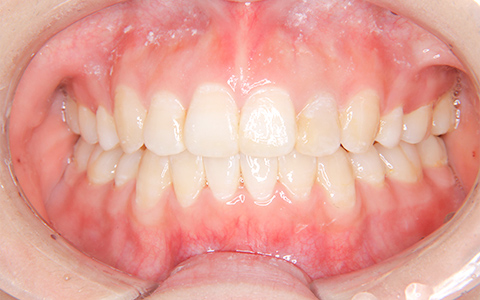

CASE.3

治療前

治療後

施術内容 右上3番の位置が気になるとのことでご来院(16歳)。犬歯の異所萌出、上顎骨の狭窄に対するマルチブラケット装置による抜歯(上顎両側4番を抜歯)治療

治療期間 2年6ヵ月(通院30回)

費用 880,000円

リスク・副作用 歯が動く痛み、歯髄壊死、歯根吸収、歯肉退縮、リテーナーを使用しないことによる後戻り